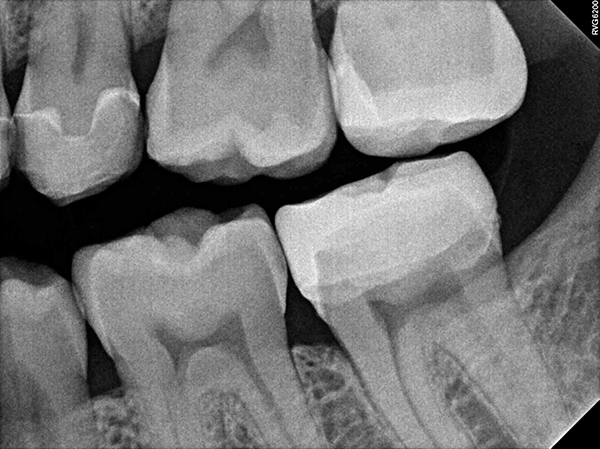

Visual examination revealed decay on the mesial marginal ridge and distal marginal ridge of tooth #13 as well as extensive buccal and occlusal decay on tooth #15 (Figs. 1-2). Bitewing radiographs and intraoral photographs were taken, which confirmed the above diagnosis and also exposed additional decay on the distal of tooth #12 (Figs. 3-4).

Fig. 3 Fig. 4

Once the milling was complete, the restorations were polished, the fit was verified and they were cemented in place (Fig. 12). Final control radiographs were acquired with the RVG 6200 intraoral sensor to confirm the fit of the inlays and crown (Figs. 13-14).

Fig. 13 Fig. 14